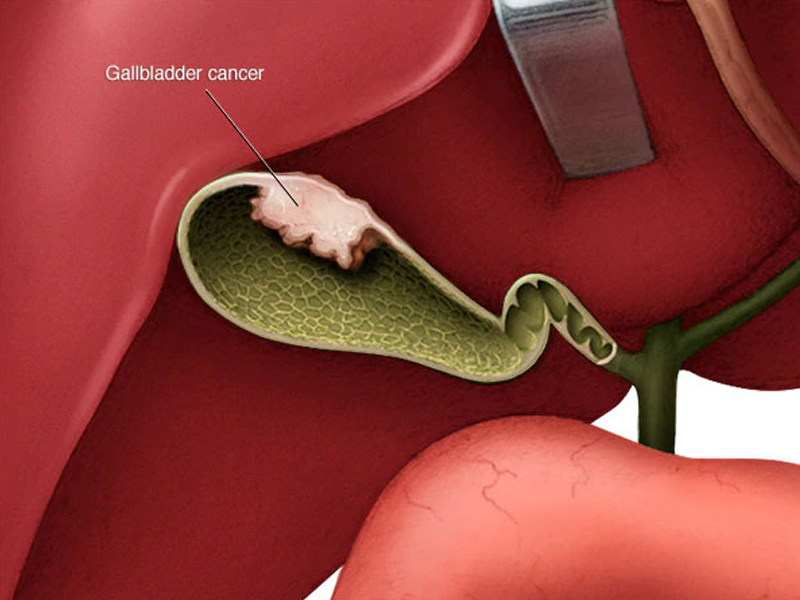

Laparoscopic Gallbladder Stone Surgery

Your gallbladder is a pear-shaped organ that stores bile, the fluid that helps digest food. If it's not working the way it should..